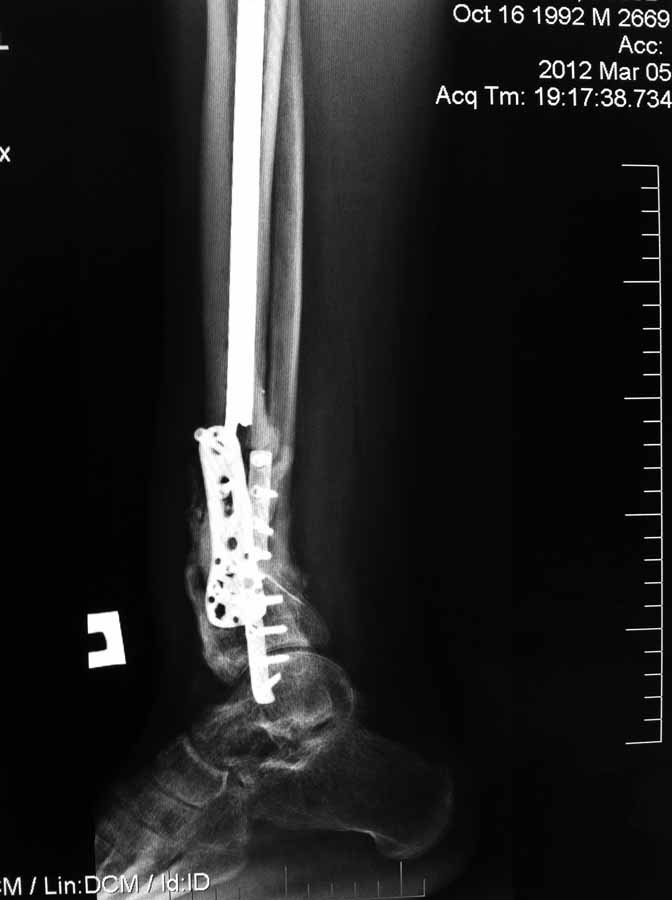

Re: Несращение дистального отдела костей голени

Вчера не вышло выслать все фото. Последние снимки более более драматичные, как раз с куском проксимального стержня и пластиной что не к месту!